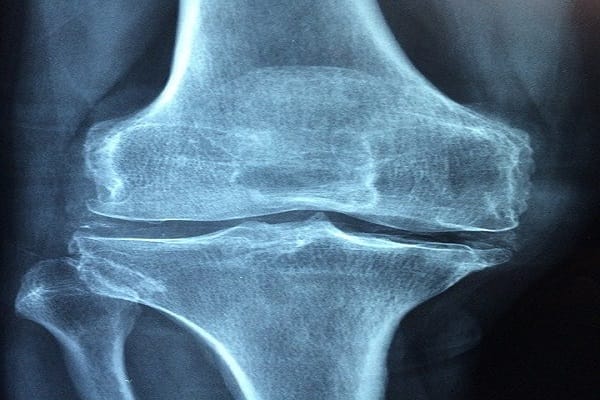

Preberite večOsteoporoza lahko tekom staranja prizadene tako žensko kot moško populacijo, saj postajajo z leti kosti krhke in lomljive. V kosteh potekata